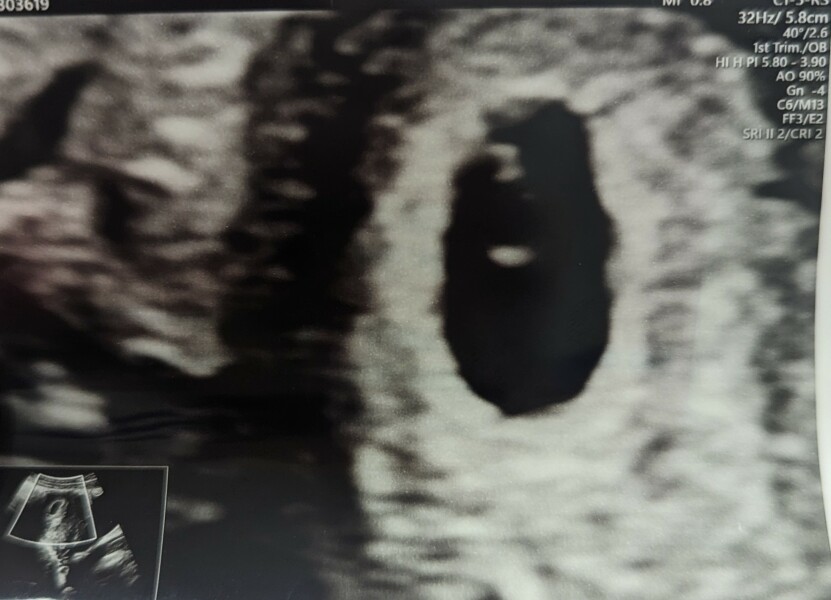

This might seem like a strange question, but I keep thinking the fetal pole in my early nhs scan (5+6) looks odd compared to all the others I can find online. Mine is bent in half?! Lol. Is it supposed to be like that? Or am I just reading the scan completely wrong? Excuse the stupid question 🙈

Zoomed in x